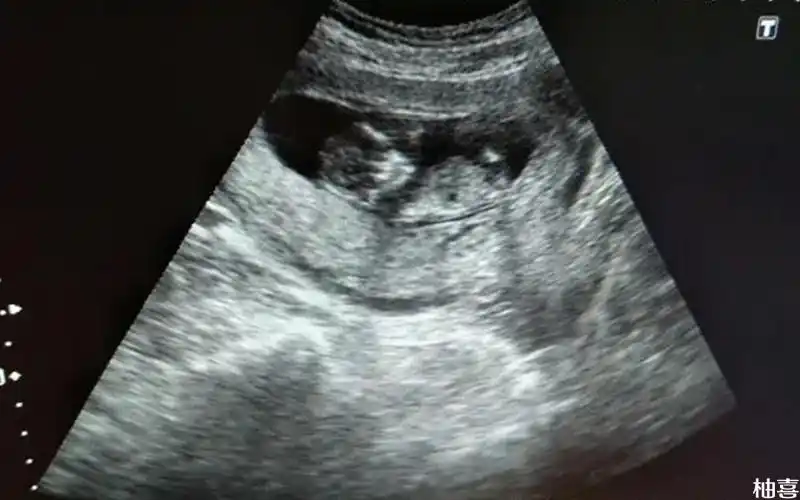

孕12周 2天延边朝鲜族自治州2020年11月 男宝54% 女宝46%

孕12周nt显示图能分辨男女吗,各位帮我看看